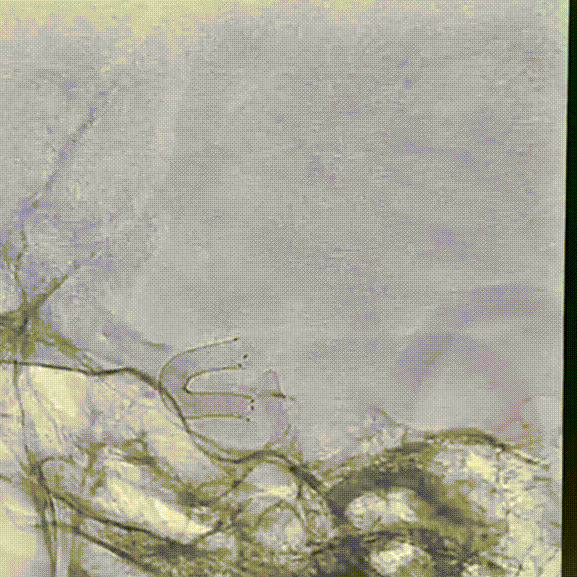

根据测量血管直径大小及长度,将0.027" 支架微导管置于大脑中动脉,推拉结合,将通桥麒麟™血流导向密网支架 3.5*20mm头端释放,泄支架微导管张力后,将支架后撤至大脑前分叉处,逐步释放支架到一半定位,观察是否覆盖大脑前动脉分叉。

确定位置可,未覆盖前分叉处,支架位置及形态可,贴壁良好,半释放通桥麒麟™血流导向密网支架 。

通桥麒麟™血流导向密网支架完全释放后造影,支架贴壁良好,位置可。

通桥麒麟™血流导向密网支架完全释放后,微导丝塑型,成攀按摩支架,使支架贴壁更佳。